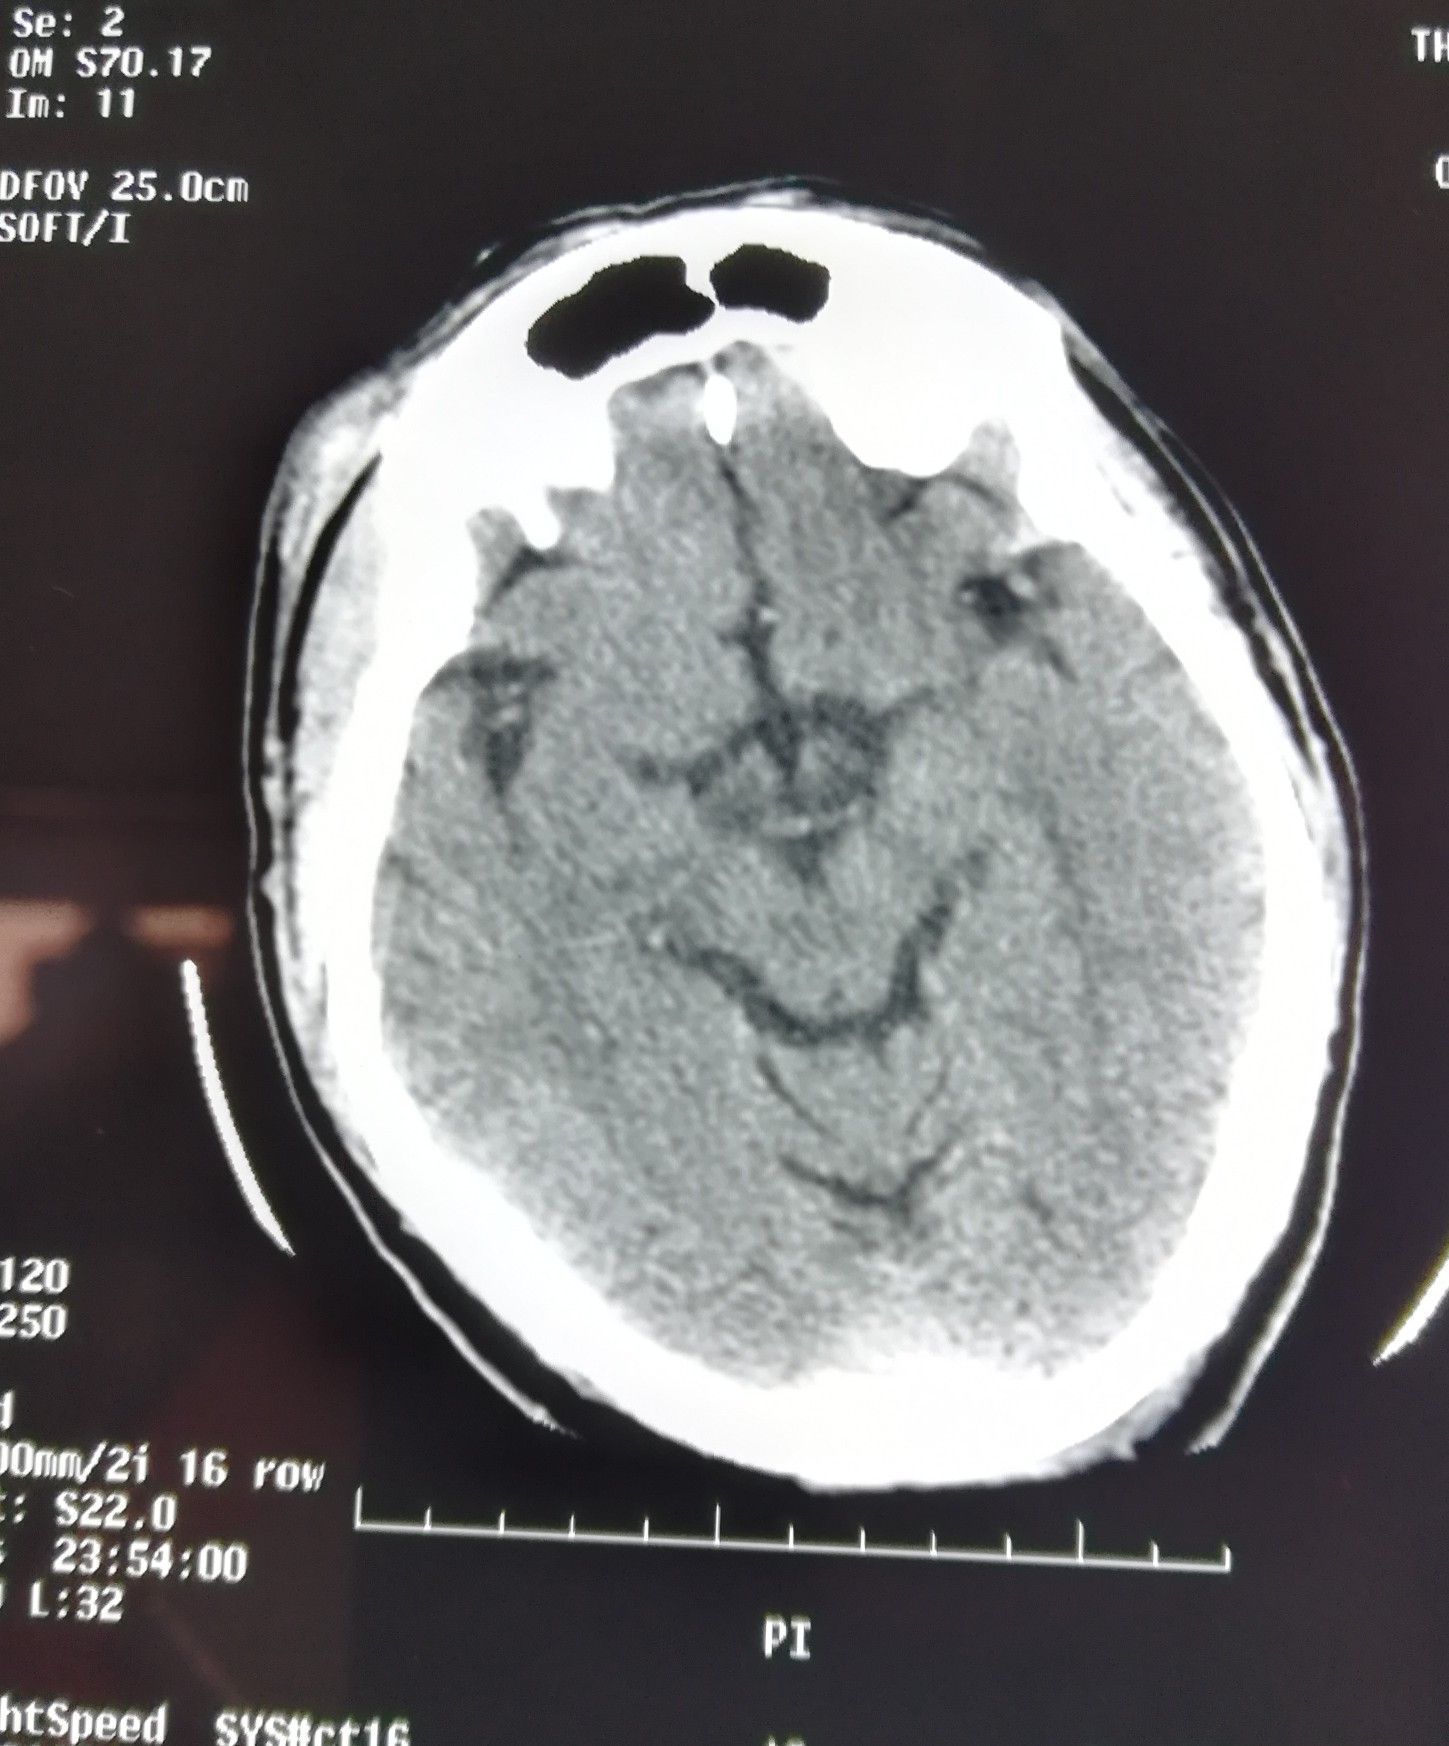

Polar Bear in NCCT

Brain

Neurology

Neurosurgery